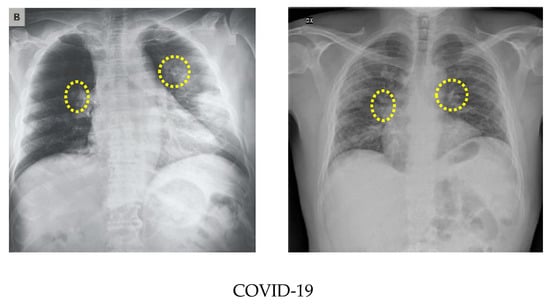

As the number of images available in the open repository was limited, the images from all three databases were combined to create a database for this work. The training and testing stages used both classes: COVID-19-positive and COVID-19-negative. The COVID-19-positive class contained 1979 images, and the COVID-19-negative class contained 3111 images. All data sets were divided into 0.8 portions and 0.2 portions for the training and testing, respectively. A computer having 64-bit windows, 8 GB RAM, Intel Core i5 CPU with a processing speed of 2.60 GHz was used for performing all training and testing. MATLAB 2019b was used to execute all necessary experiments. The experimentation times are computed with a GPU hardware configuration of GEFORCE RTX 2070 super. Figure 3 illustrates a comparison of the COVID-19 and normal chest X-ray images. In general, similar to pneumonia, the density of the lungs is increased in the case of the COVID-19, which causes whiteness in the lungs on radiography. An experienced radiologist can confirm the disease by the appearance of a ground-glass pattern (ground-glass opacity) due to the increased whiteness [46].

Figure 3.

Comparison of the COVID-19 and normal X-ray images.